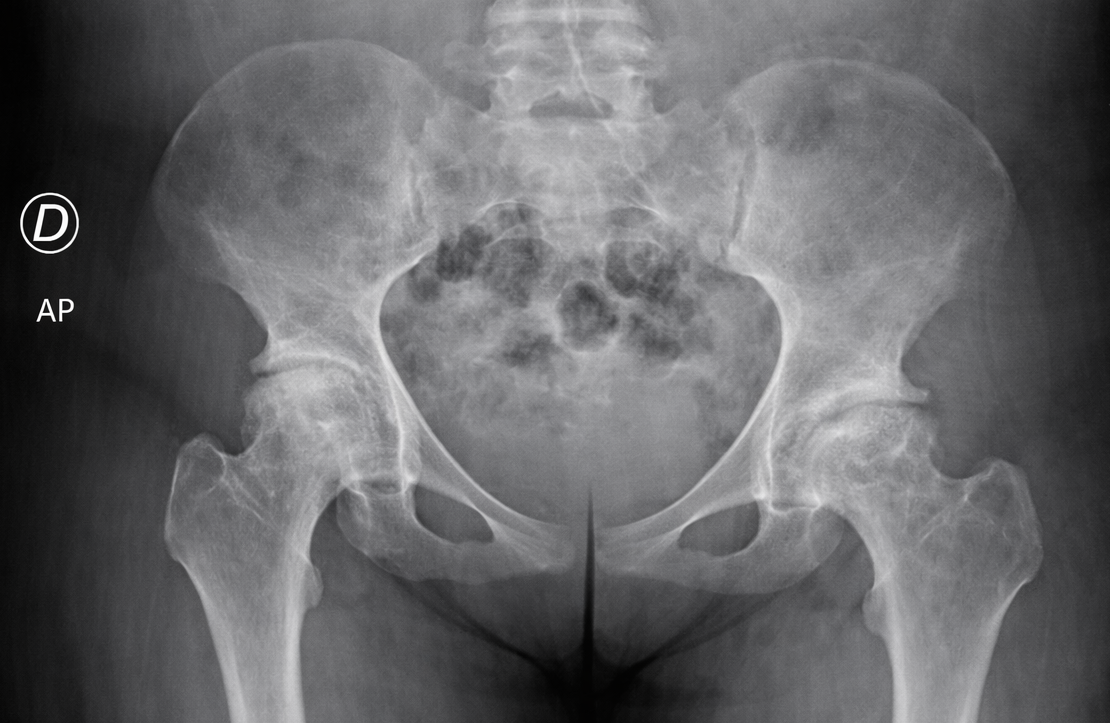

Osteonecrosis of the femoral head (Figure 1) is one of the most common and debilitating orthopedic complications of SCD. It is estimated that nearly 50% of affected patients will experience avascular necrosis of a major joint during their lifetime, and a significant proportion will ultimately require total hip arthroplasty (THA). These patients often present with a distinctive phenotype, characterized by a slender body habitus, low muscle mass, elongated limbs, and an overall asthenic appearance. From a metabolic and skeletal standpoint, chronic hemolytic anemia, marrow hyperplasia, and reduced bone mineral density are frequently encountered.